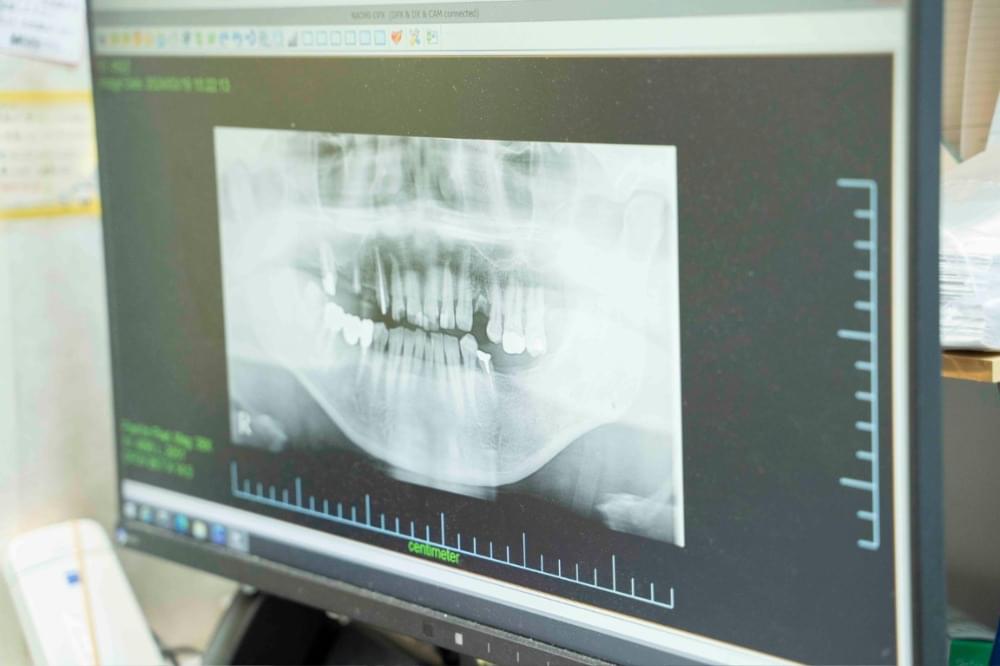

歯を失う原因の第1位は虫歯ですが、歯周病も虫歯の次に歯を失う大きな原因になっています。特に40歳あたりからは、歯周病の比率が高くなってきます。歯の周りには、歯を支える様々な組織(歯肉、歯根膜、セメント質、歯槽骨)があります。歯周病は、これらの組織が細菌に感染して起こり、次第に歯を支えている骨(歯槽骨)が溶けていく病気です。虫歯は歯が溶ける病気ですが、歯周病は骨が溶ける病気なのです。